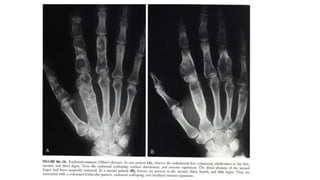

Subcutaneous nodules. Observe the prominent

soft tissue nodules in the second and third

digits, with acro-osteolysis of the terminal

tufts.

 Highly probablesarcoid arthritis includes the typical features of the trabecular pattern, osteolysis, cyst formation, and punched-out lesions

Subcutaneous nodules. Observethe prominent soft tissue nodules in the second and third digits, with acro-osteolysis of the terminal tufts.